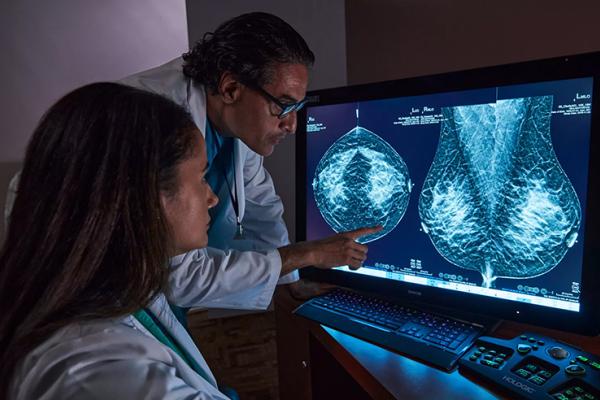

Raise your breast cancer screening performance1-4 with C-View software and instantly generated synthesised 2D images. It not only enhances details and speeds up the analysis, but also reduces radiation dose levels for your patients. C-View 2D images are clinically proven3,5 and FDA approved to diagnostically replace the FFDM images within a tomosynthesis screening exam.

Architectural distortions, mass lesions, and bright spots commonly found in microcalcifications are more visible in the C-View 2D image than on the traditional FFDM 2D images or tomo slices.4,6-9

C-View 2D images are clinically proven3,5 and FDA approved to diagnostically replace the FFDM images within a tomosynthesis screening exam. The images are also a navigational aid to the tomosynthesis slice review. Published studies show that the low dose 3D Mammography exam finds invasive cancer earlier, while also reducing false positive recall rates compared to 2D alone.4,5,7

Architectural distortions, mass lesions, and bright spots commonly found in microcalcifications, are more visible in the C-View 2D image than on the traditional FFDM 2D image or tomo slice.4,6-9